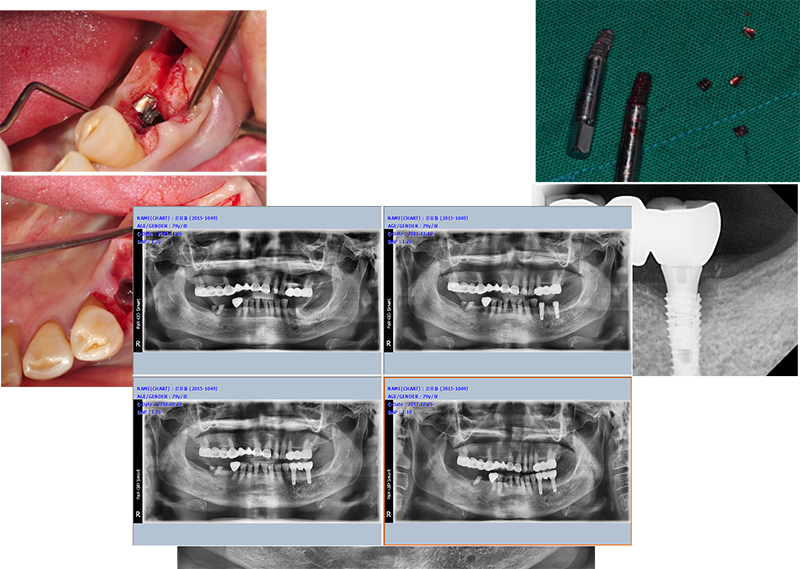

이 임상 케이스는 브릿지 타입을

싱글 타입으로 바꿔주기 위한 작업 중 일어난 작은 소동을 기록했다.

어벗을 풀다가 플렛폼에 있는

헥사가 망가졌다. 풀 수가 없었다. 4.4 mm 내경을 가진 solid ab 체결 드라이브를 이용하기로 했다.

먼저 Ezc 어벗의 직경을 다이아몬드 버로 살짝 다듬은 다음, 슬롯을 만들고, 이곳에 solid ab 드라이버가 삽입되도록 한다. 돌리면 쉽게 제거된다.

잇몸이 웃자랐다.

Ext. type 3.75mm 직경의 임플란트.

Bruxism 이 있는 환자로써 심고 기능한 지 15년 만에 부러져서 내원했다.

직경이 3.75mm로 예전 regular에 해당하지만 4.0mm보다 부러지는 경우가 많다.

또한 Ext은 보철이 올라가면 플랫폼에서 1.5mm 골흡수가 거의 필연적으로 일어난다. 이번 경우도 골흡수와 깊은 연관이 있다고 여겨진다.

앞에서 얘기한 것처럼 제일 중요한 것은 “변 연골 흡수”가 일어나지 말아야 한다.